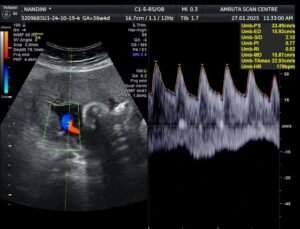

1. What is a Doppler check scan in pregnancy?

A Doppler check is done to evaluate blood flow in the umbilical artery and the middle cerebral artery in the baby’s brain. It is done along with the AFI check if there is growth restriction or a high-risk condition like hypertension

6. When is this Doppler check performed?

Doppler scans are often done in the second or third trimester for high-risk pregnancies, intrauterine growth restriction (IUGR), hypertension or if there are concerns about your baby’s health or previous scans are showing a reduced flow.